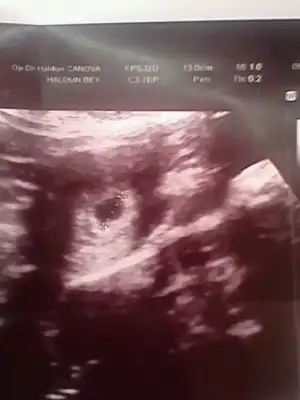

Var cnm hemen hemen herkesin ayni gibi eklemeye calsiirimarkadaslar lütfen bi bakin. benim bu ultrason fotom 5+5 . doktor birsey demedi gerci bebek ve kalp atisini haftaya görebiliriz dedi sadece yolk kesesini görmüstük ama bana normal gebelik kesesi kücük geldi. sizce nasil elinde böyle fotosu olan var mi baska

Benimkinde 13mm yaziyor usttekesen 5 mm canım

Benimkinde 13mm yaziyor ustte

bakalım benim kaç çıkacak yarın gidicemBuda benimki